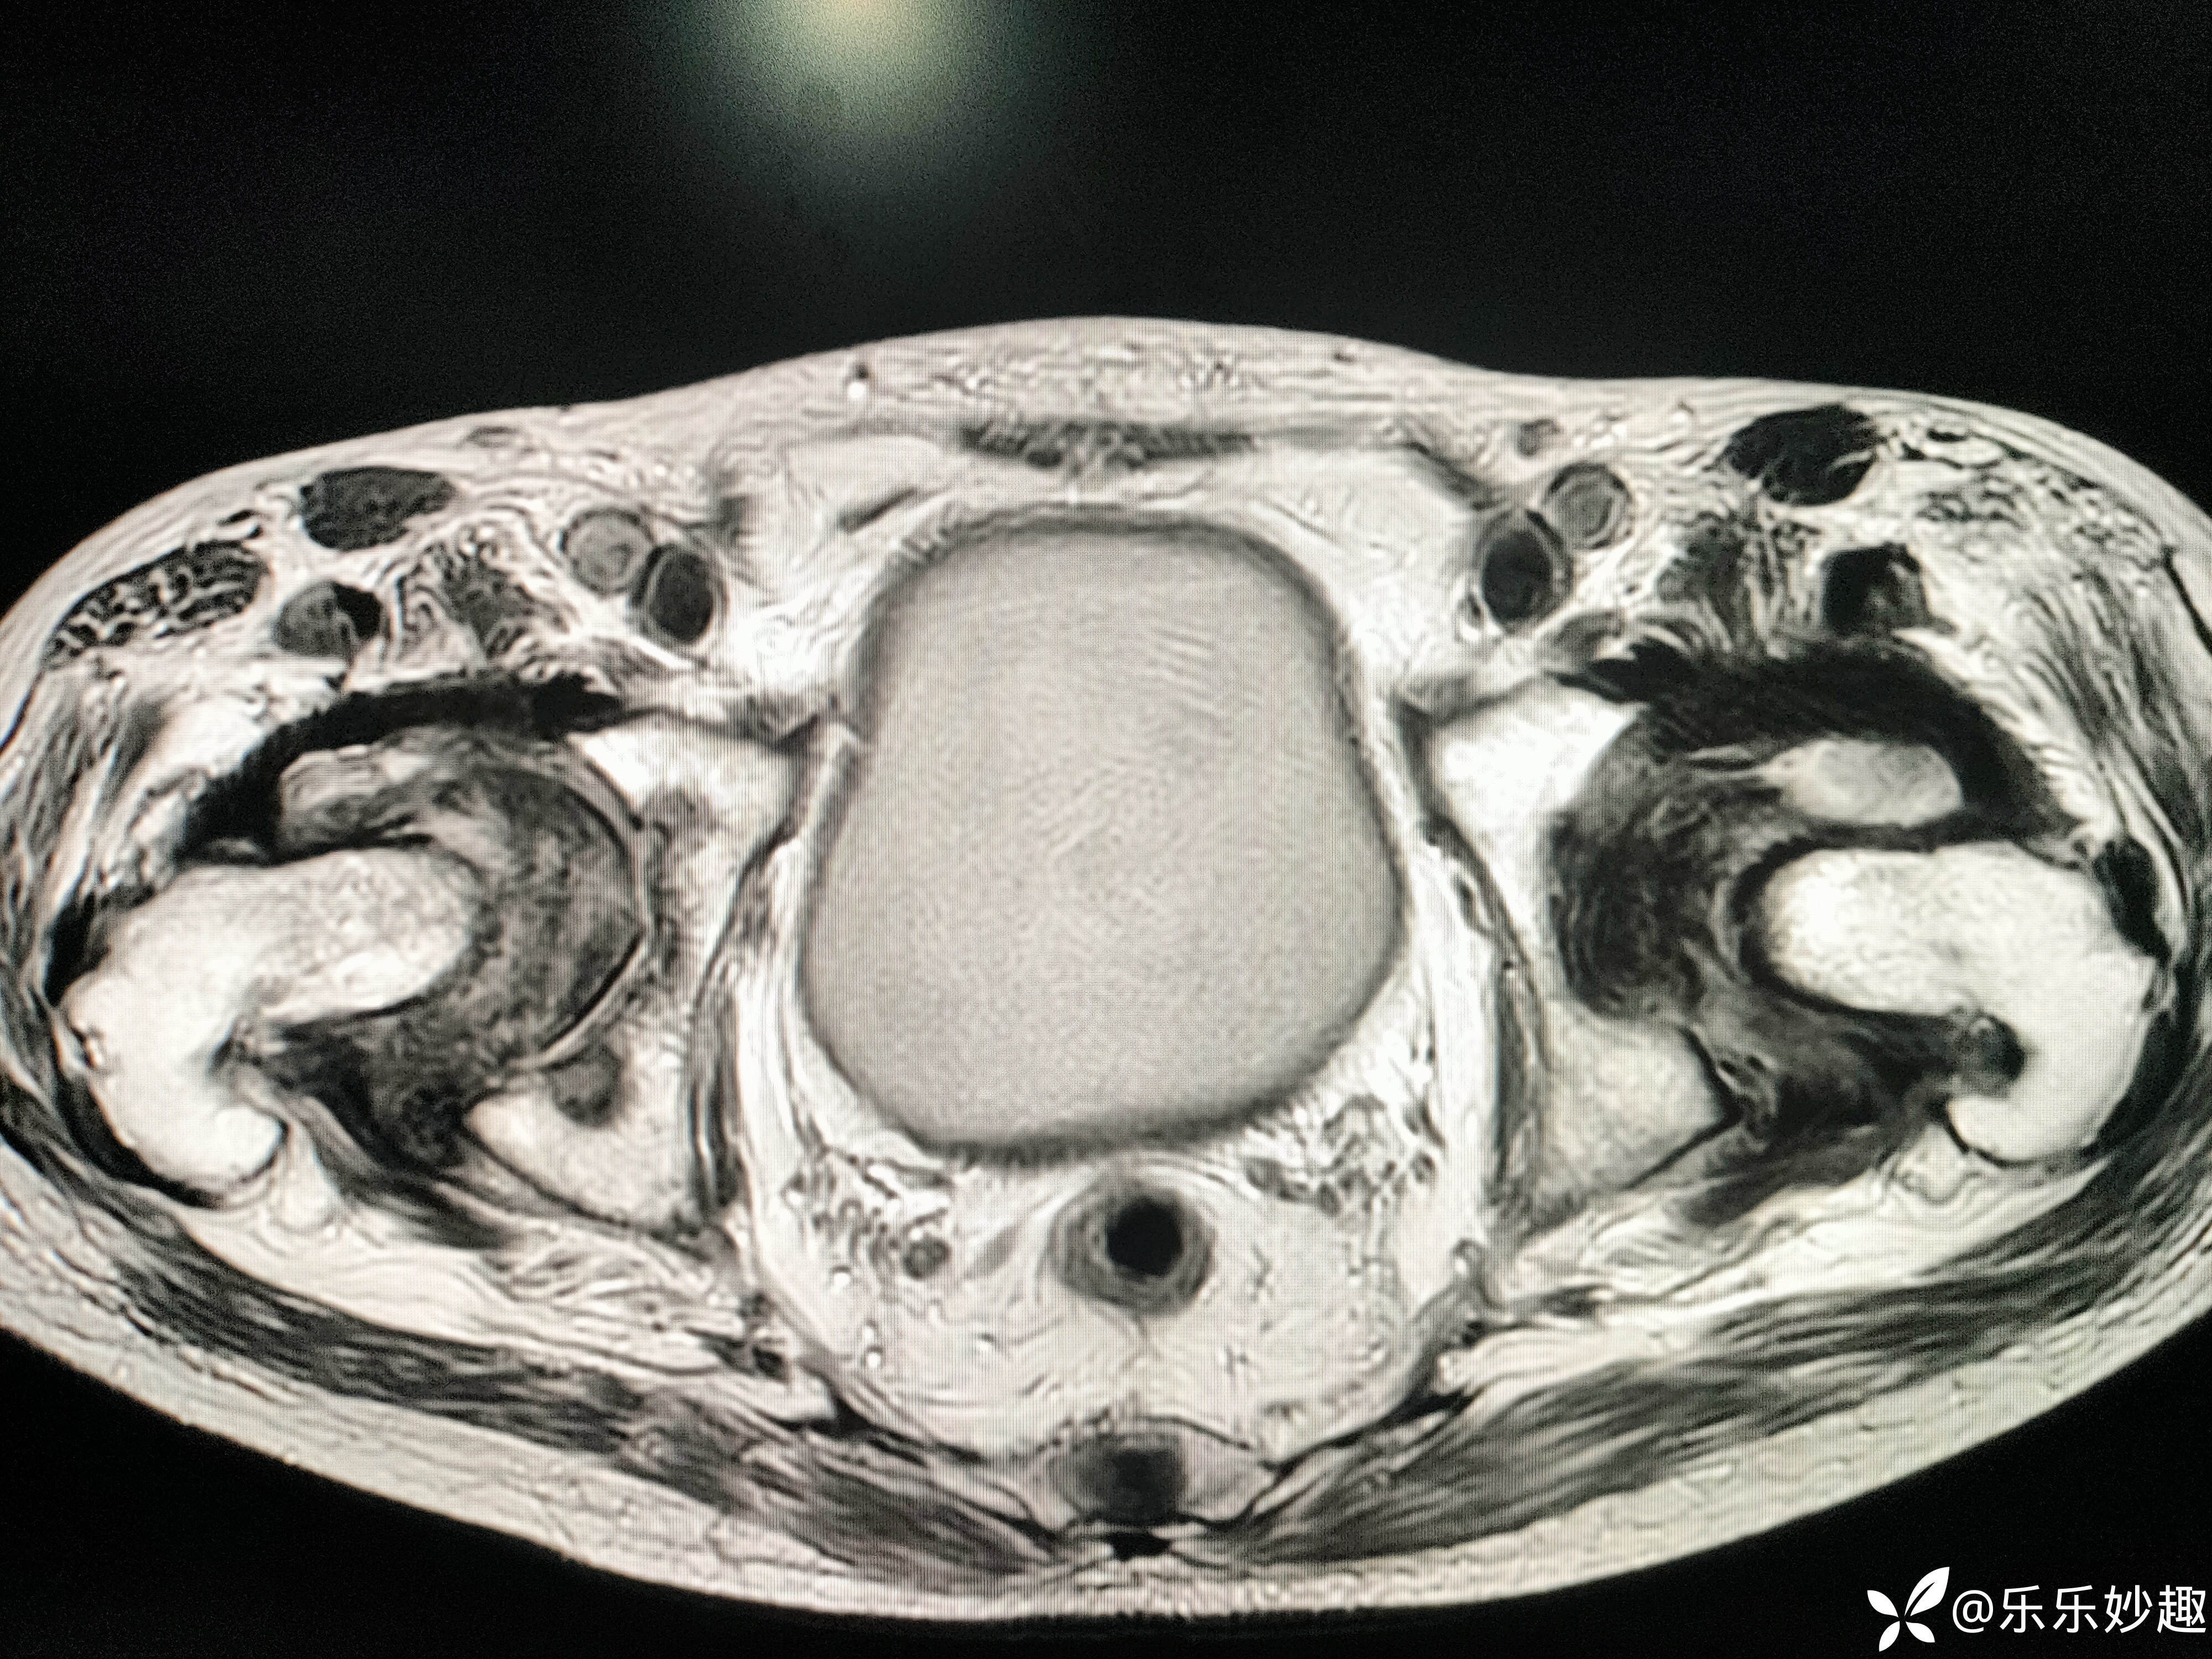

然后做了CT,见下图